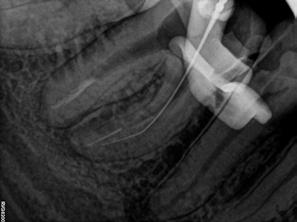

A terület érzéstelenítését és kofferdám felhelyezését követően a meglévő kompozittömést eltávolítottuk és a gyökértömés elkészítéséhez szükséges körülmények biztosításához folyékony kompozit és folyékony kofferdám felhasználásával egy ideiglenes felépítményt készítettünk (14–17. ábra). Ezt követően eltávolítottuk a gyökértömő anyagot a mesialis és a disztális gyökércsatornákból. A betört eszközökhöz való hozzáférés biztosítását követően a magasabban elhelyezkedő fragmentumot egy ultrahangos eszköz segítségével eltávolítottuk (18. ábra). Ezután a mélyebben fekvő darab koronális vége is láthatóvá vált. Sajnos az eltávolítandó gyökérkezelő tű a közepén kettétört és csak a koronálisabban fekvő részét sikerült eltávolítani (19. ábra). Mivel az apikális fragmentumra nem láttunk rá közvetlenül és az átöblítés, valamint aktiválás hatására sem emelkedett ki a csatornából, ezért az eszköz mellett történő elhaladás megkísérlése mellett döntöttünk. A CBCT-felvétel tanulmányozása során nem tudtuk egyértelműen megállapítani, hogy a két mesialis csatornának vajon egy közös vagy két különálló kivezetőnyílása van, ezért a mesiolingualis csatorna megmunkálása közben periapikális röntgenfelvételt készítettünk. A röntgenfelvétel alapján vagy egy lépcső-

képződés alakult ki a csatornán belül, vagy a mesialis gyökér két különálló kivezetőnyílással rendelkezik (20. ábra). A gyökércsatorna átöblítése során 300/20 SWEEPS vezetőszálat

alkalmaztunk (AutoSWEEPS üzemmód; 1,2 W).

közleményekben már ismertetett „Less-Prep Endo” protokollnak megfelelően végeztük. Az átöblítés során erőteljes áramlást észleltünk a mesialis csatornák között. [5] A csatornákat elszívás és steril papírpoénok segítségével szárítottuk ki (21. ábra). Ebben az állapotban sem éreztük a csatornák teljes átjárhatóságát és csak a mesiolingualis csatornának megfelelően éreztünk tugbacket. A mesiobuccalis és a disztalis csatornát epoxi-rezin alapú sealerrel töltöttük fel, majd a csatornákba meleg guttaperchát injektáltunk (squirting technique). A mesiolingualis csatornába egy 4%-os konicitással rendelkező #30-as guttapercha mesterpoént helyeztünk, amelyet continuous wave kondenzációs technikával tömörítettünk (22. ábra). Végső kontrollként egy disztoexcentrikus irányú periapikális röntgen készült (23. ábra). A felvételen a mesialis gyökércsúcs körül látható sealer puff, valamint hirdetés

28. ábra: A kofferdám felhelyezését követően látható állapot. – 29. ábra: A maradék szuvasság eltávolítása és a folyékony kofferdámfelhelyezést követően látható klinikai helyzet. – 30. ábra: A gyökértömés eltávolítása. – 31. ábra: A felvételen egyértelműen láthatóak a gyökércsatorna-bemenet körül végzett jelentős mennyiségű pericervicalis dentin eltávolításának nyomai. A foganyagot valószínűleg ultrahangos eszközökkel távolították el, miközben a betört eszköz eltávolításához szükséges hozzáférést próbálták biztosítani. – 32. ábra: A gyökércsatorna-bemenet részleges helyreállítása folyékony kompozit segítségével. 33. ábra: A mesiobuccalis csatornában lévő gyökérkezelő tűk vége egyértelműen felismerhető.

20. ábra: A radiológiai felvétel igazolja, hogy nem tudtunk a betört eszköz mellett elhaladni. – 21. ábra: Az átöblítést követően látható állapot. – 22. ábra: A gyökértömés elkészítését követően látható állapot. – 23. ábra: Kontrollröntgen.

behelyezett guttapercha poénokat az összes csatornából eltávolítottuk (30. ábra). A gyökércsatornák és a fogbélkamra megtisztítása során megállapítottuk, hogy a mesiobuccalis gyökércsatorna bemenete körül korábban jelentős mennyiségű dentint távolítottak el (31. ábra). Ezt valószínűleg a betört eszköz eltávolítására tett kísérletek során végezték el. Szerencsére nem észleltünk perforációra utaló jeleket az adott területen.

A meggyengített részeket kompozit segítségével töltöttük fel (32. ábra).

A mesiobuccalis csatornát NaOCl-oldattal töltöttük fel, majd az átöblítőszert AutoSWEEPS üzemmódban

alkalmazott lézerkészülékkel aktiváltuk. A terület nagy nagyításban történő megfigyelése során (x16) két betört eszközfragmentumot azonosítottunk, amely még komplexebbé tette ezt az esetet (33. ábra). Mindkét fragmentum koronális része

tattak elmozdulási hajlamot, ezért lézeres aktiválással próbálkoztunk (AutoSWEEPS üzemmód; 1,2 W; lapos SWEEPS 300/20 vezetőszál). Átöblítőszerként NaOCl-t és EDTA oldatot alkalmaztunk. Néhány perc után mindkét fragmens kismértékű mobilitást mutatott, amely arra utalt, hogy az eltávolításuk lehetséges lehet. Végül mindkét eszközdarabot egy endolasszóval sikerült eltávolítani (BTR Pen, CERKAMED) (34. ábra). Az eltávolítás sikerességét periapikális röntgenfelvétel segítségével igazoltuk (35. ábra).

A betört eszközök eltávolítását követően az összes csatornát gépi tágítók segítségével munkáltuk meg, majd a végső átöblítési protokoll során az átöblítőszereket ultrarövid impulzusokkal (super-short pulse; SSP) aktiváltuk. Az átöblítés befejezésekor erőteljes áramlást észleltünk a mesiobuccalis és a mesiolingualis csatornák között. A csatornák szárítását követően megállapítottuk, hogy a mesialis csatornabemenetek nagysága közel azonos, amelyből az következik, hogy a betört eszközök eltávolítása konzervatív módon történt, mivel nem került kifejezett mennyiségű foganyag eltávolításra (36. ábra). A gyökértömés készítése során a csatornákat epoxi-rezin sealerrel töltöttük fel, majd a guttaperchát continuous

wave technikával kondenzáltuk (37. ábra). Végső kontrollfelvételként egy disztoexcentrikus irányból készült periapikális röntgenfelvételt készítettünk, amelyen egyértelműen látható, hogy a két mesialis gyökércsatorna közti teret a gyökértömő anyag jól kitöltötte (38. ábra). Ezt követően a fogat üvegszálas csappal megerősítettük, majd visszairányítottuk a kezelőorvosához, aki egy indirekt restaurátummal fedte. Tizenkét hónappal később kontroll CBCT-felvételt készítettünk (39. ábra). A felvételen nem voltak gyulladás jelei láthatóak, valamint a páciens is teljesen panaszmentes volt.

36. ábra: Az átöblítést követően látható állapot. – 37. ábra: A gyökértömés elkészítését követően látható klinikai helyzet. – 38.

kontrollröntgen. – 39. a–b ábra: Tizenkét hónappal később készített kontroll CBCT.